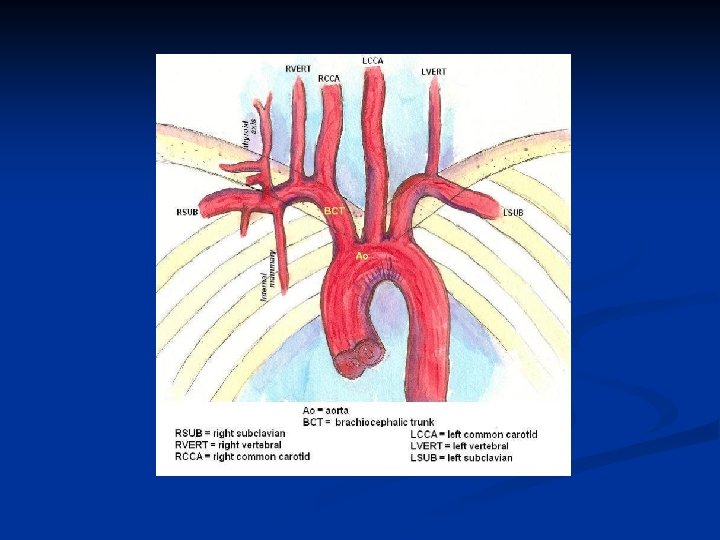

Anatomy n Aortic Arch n Innominate or Brachiocephalic artery n Right subclavian artery n Right common carotid Left common carotid artery n Left subclavian artery n n CCAs lie posterolateral to thyroid n Deep to sternocleidomastoid muscle n

Anatomy Right CCA originates from innominate artery n Left CCA originates from aortic arch n CCAs divide into ECA and ICA n ICA has no branching vessels in the neck; may have slight dilation just past its origin; supplies face and head; lies posterior in the neck n ECA has branching vessels; usually smaller than ICA n n Vertebral Arteries – lie between transverse

Answers to previous slide Aortic arch angiogram n 1. Innominate art. n 2. Right subclavian art. n 3. Right common carotid art. n 4. Right vertebral art. n 5. Left common carotid art. n 6. Left vertebral art. n 7. Left subclavian art.